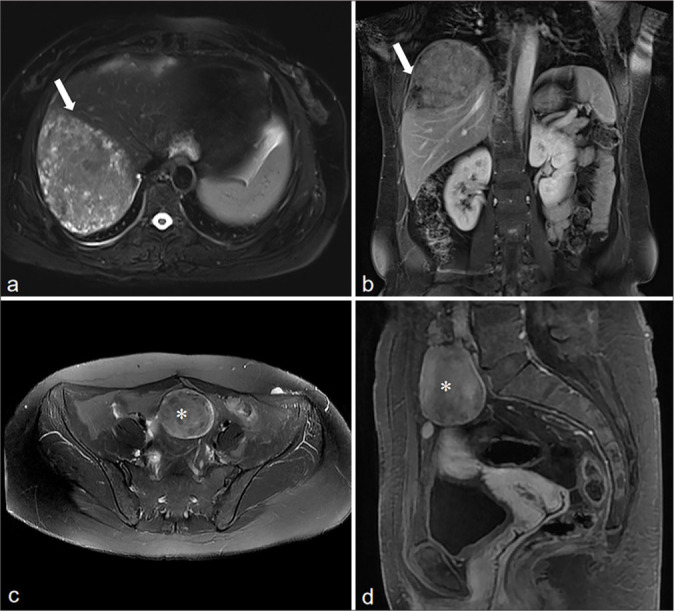

Results: All the 10 LPD patients presented with multifocal lesions in the abdomen and pelvis, and 7 of them had a history of hysteromyoma surgery. The number of lesions was all ≥2, most of them were round or quasi-circular, with clear boundaries and smooth edges, did not invade the neighboring parenchymal organs, with a length of about 1.5~16.8 cm. The lesions were located in the pelvic cavity in 6 cases, the abdominal wall in 6 cases, the intestinal wall in 3 cases, the rectouterine pouch in 1 case, the omentum in 5 cases, the abdominal cavity in 1 case, and the mesentery in 1 case. There were 7 cases with minimal pelvic fluid and 1 case with liver spread. CT showed circular solid nodules with clear boundaries. The density of small lesions was homogeneous. Cystic changes were observed in some large lesions. On MRI, T1-weighted imaging showed hypo to isointense, T2-weighted imaging (T2WI) mostly showed hypointense, and T2WI in some large lesions showed slightly high signal intensity, diffusion-weighted imaging signal intensity was not higher than that of myometrium, apparent diffusion coefficient showed isointense, and solid components of the lesions were significantly more homogeneous enhanced after enhancement, and the enhancement degree was similar to that of normal myometrium.